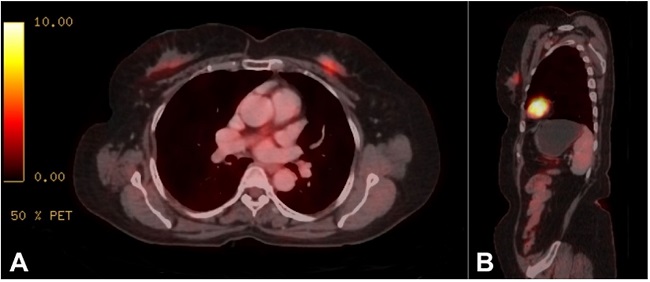

A 65-year-old female, with no family history of any malignancy, had presented with a palpable lump in the left breast (upper inner quadrant) associated with bloody nipple discharge of 3 months duration at a peripheral hospital. Sono-mammography revealed a solitary, solid, and incompressible hypoechoic nodule in the retroareolar region, measuring 17.5 x 9 mm, with heterogeneous echotexture and irregular margins, consistent with Breast Imaging Reporting and Data System (BIRADS).3 The patient underwent fine-needle aspiration cytology (FNAC) of the lesion, which was suspected of malignancy. Subsequent core biopsy of the lump was diagnosed as Invasive Lobular Carcinoma. FDG-PET scan revealed an ill-defined, hypermetabolic, heterogeneously enhancing soft tissue nodular lesion involving the upper inner quadrant of the left breast measuring 13 x 9 x 25 mm, with SUV max 4.6 (Figure 1).

Mammography detection rates of this tumor range around 50%. Thus, many of the tumors may be mammographically occult.10 Ultrasonography detects around 50% of these tumors as BIRADS-4 or BIRADS-5 lesions. The ultrasonographic features include “frond-like” mass, either solid or complex cystic, within a dilated duct.11 The magnetic resonance imaging (MRI) is another radiological investigation tool with high sensitivity for detecting SPCs.10 A study has highlighted some characteristic features of SPC on MRI, including circumscribed lesion’s margins with heterogeneous signal intensity and rapid enhancement in the initial contrast phase and high apparent diffusion coefficient values with the absence of choline peak. These features may help to distinguish SPC from other invasive breast malignancies.12 The sono-mammography features of our case showed a hard and incompressible left breast mass with heterogeneous echotexture and irregular margins with spiculations, without any cystic changes or necrosis, consistent with BIRADS III lesion. Our patient was not submitted to an MRI study. FDG-PET scan, which is mainly done for the staging, restaging, and evaluation of treatment response in breast cancers, revealed a hypermetabolic soft tissue nodular lesion in the upper inner quadrant of the left breast with no other significant metabolic active disease elsewhere in the body. She was misdiagnosed as a case of ILC on a small biopsy.